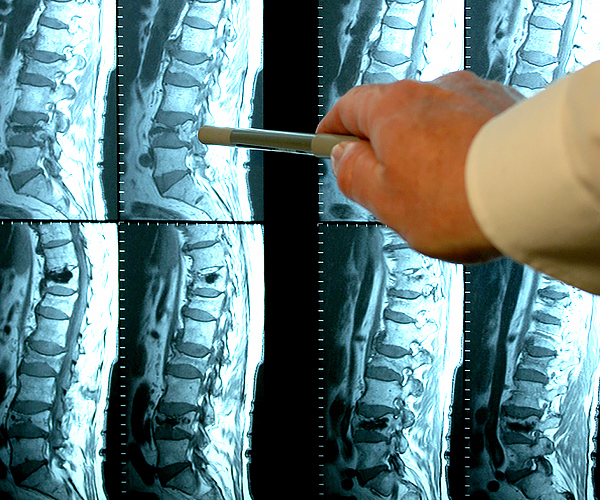

Femme de 54 ans. Son articulation est entièrement restaurée. La durée du traitement : 14 jours :